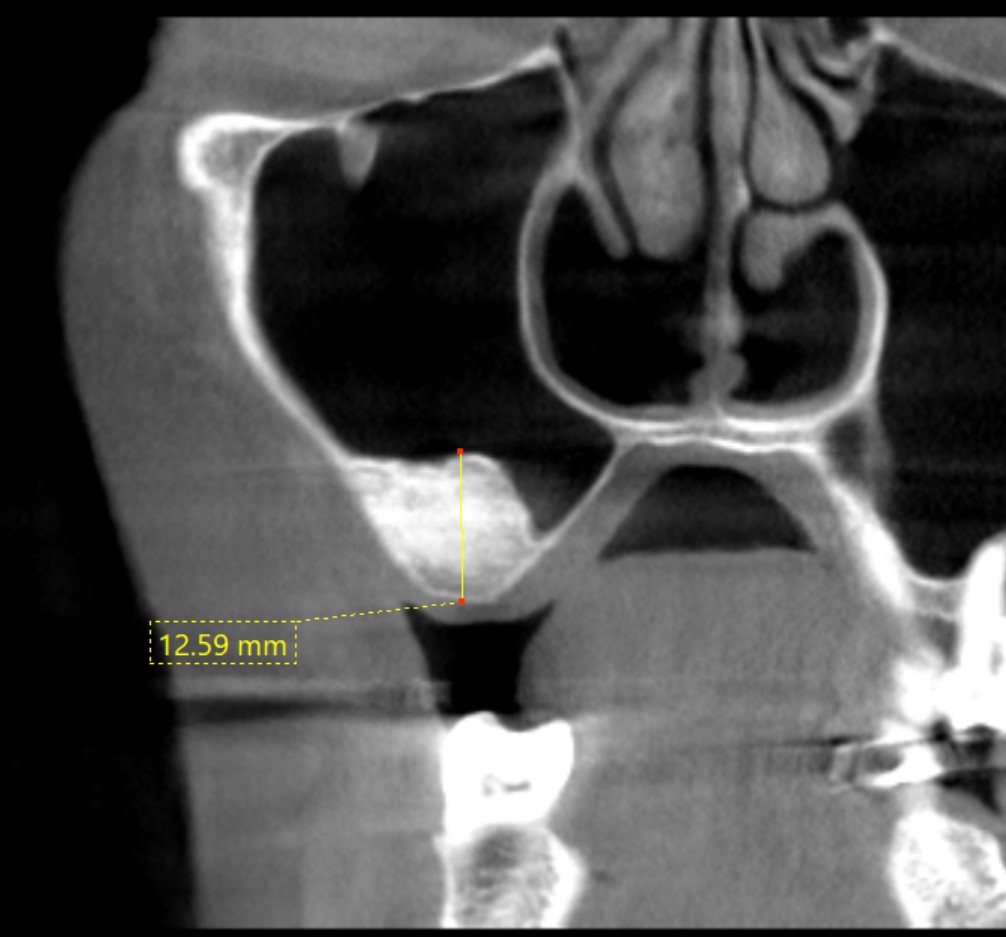

上顎奥歯部の骨量不足に対して、

**サイナスリフト(上顎洞底挙上術)**を行い、骨の高さを確保したうえでインプラントを埋入しました。

サイナスリフト後、治癒期間をおいて十分な骨の形成を確認し、インプラントを埋入しました。

初診時

術後